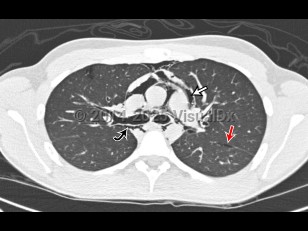

Pneumomediastinum in Infant/Neonate

Pneumomediastinum is the presence of air in the mediastinum. It is caused by injury, most often esophageal or intestinal perforation. It can rarely occur spontaneously in children with acute asthma attacks (severe cough) and is also seen as a result of aggressive bag-valve mask ventilation during resuscitation and intubation as well as a result of barotrauma in intubated patients.